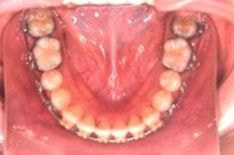

メリット

* 発音に影響が少なく、違和感も少ない

デメリット

* 下だけ表側の装置で目立ちにくいが、若干下の装置が見える

上の歯のみ裏側に装置を装着し、下の歯は表側に装着する方法も選択できます。

これは、下の装置は見えますが、舌の違和感がなくなり、発音しやすいという利点が あります。